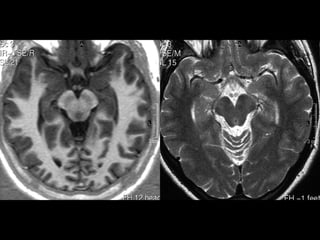

CENTRO SEMIOVAL/COROA RADIATA

MESENCÉFALO

COLÍCULOS

SUPERIORES

INFERIORES

• TETO MESENCEFÁLICO (LÂMINA QUADRIGEMINAL)

• PEDÚNCULOS CEREBELARES SUPERIORES E

• IV VENTRÍCULO

• CEREBELO - HEMISFÉRIOS

PONTE / BULBO

CEREBELO

VERMIS

TONSILAS

NÚCLEO

DENTADO

HEMISFÉRIO

CEREBELAR